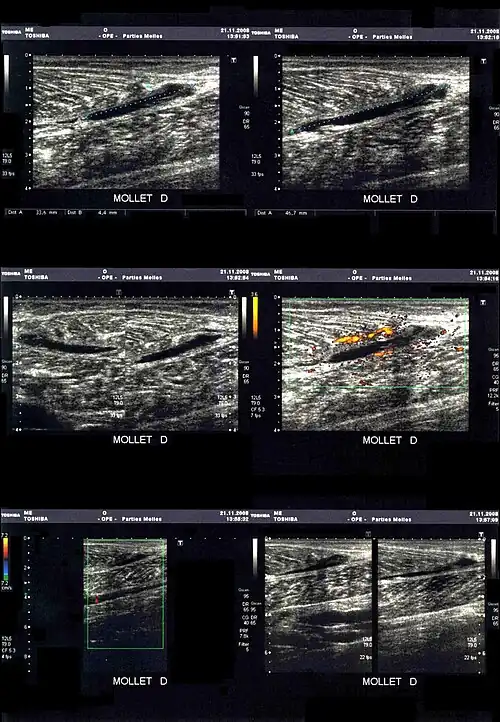

La déchirure apparait sous la forme d'une zone hypoéchogène (sans écho, et donc noire).

En cas de doute ou pour préciser les dégâts musculaires dans les cas les plus graves, une déchirure peut être mise en évidence par l'imagerie médicale[15] :

- échographie/échotomographie : « examen le plus utile et le moins cher, permet une étude des fibres musculaires, des tendons et des aponévroses. Ses limitations sont la mauvaise analyse des zones profondes, comme l’insertion proximale des ischio-jambiers, et la difficulté à détecter parfois les cicatrices »[3].